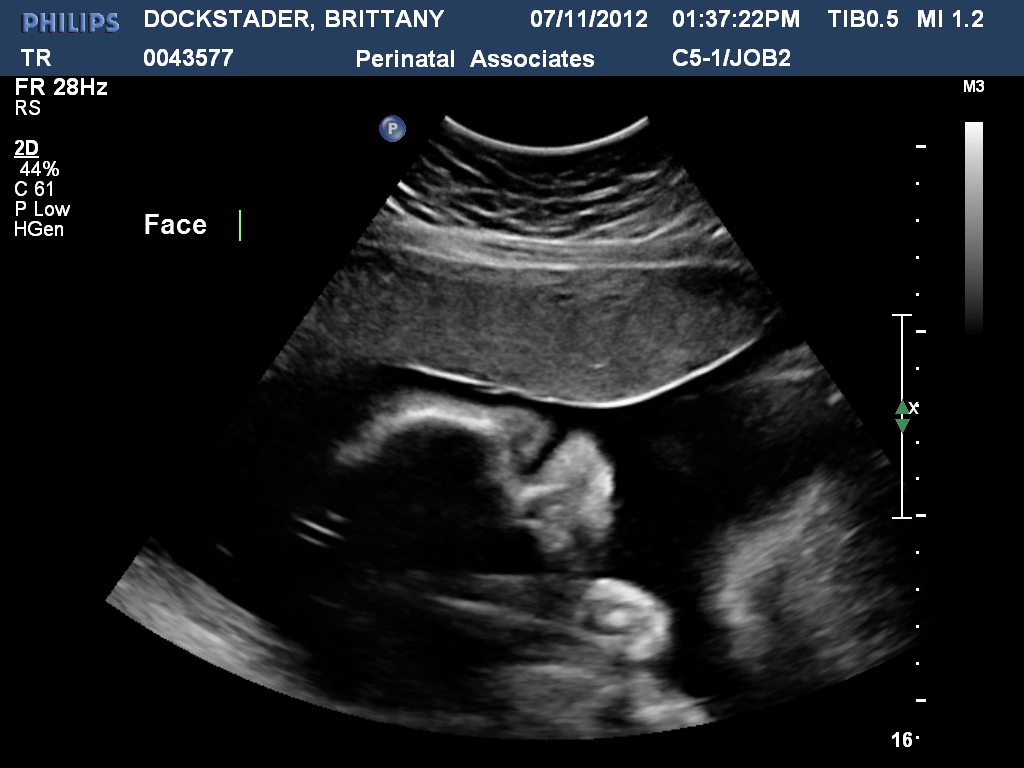

This week Dustin and I went to our regular 4 week check-up with Dr. Helm's office. I'm just about 28 weeks along! The ultrasound tech said Colton is looking great! He is measuring 29 weeks, 2 days which is great because he's going to be delivered early. Colton is measuirng 82% overall. Yay! We were able to get a few more 3D pictures today! It was so fun to see his little face! I enjoyed having Dustin at this appointment not only to share with him but because he probably won't be able to make it to anymore appointments! He starts his new job this week and doesn't get vacation days for a while! But we are excited for his new job! :) Here are the pictures!